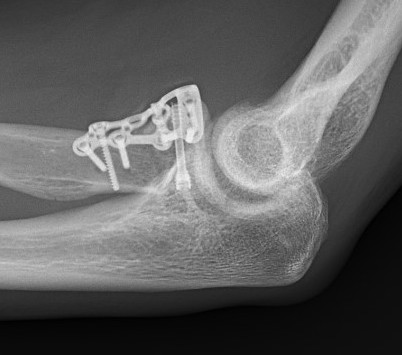

Radial Head Arthroplasty (RHA)

Design

Cobalt chrome / pyrocarbon / titanium

Modular - various head diameter / thickness + various stem sizes + collars to build up radial neck if required

Fixation - press fit v loose fit

Technique Modular Titanium Radial Head Arthroplasty

Lateral approach to elbow / Kaplans or Kocher

- open capsule

- divide annular ligaments

- excise radial head fragments

- use fragments to estimate diameter and thickness of radial head

- if in doubt, downsize

- deliver radial neck

- do not place Hohman retractor anteriorly to protect PIN

- ensure neck cut flat to avoid maltracking

- want 60% contact of radial neck with prosthesis

- insert trial broaches into neck

- insert trial head diameter and neck length

- check no overstuffing on xray

- insert prosthesis

- repair annular ligament

- inspect +/- repair LCL